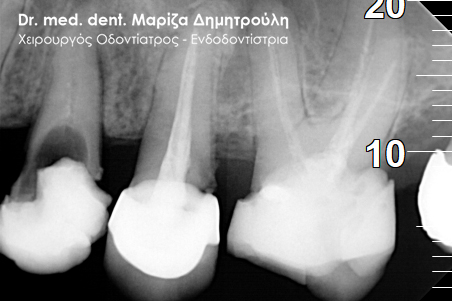

Περιστατικό – Ολοκεραμική στεφάνη / θήκη ζιρκονίου στον άνω αριστερό γομφίο

Η ασθενής επισκέφτηκε το ιατρείο μας γιατί πονούσε στον πρώτο άνω αριστερό γομφίο. Η κλινική και ακτινογραφική εξέταση φανέρωσε την αναγκαιότητα απονεύρωσης του δοντιού. Μετά το πέρας της ενδοδοντικής θεραπείας και εφόσον το οδοντικό έλλειμα ήταν μεγάλο, κρίθηκε απαραίτητη η προστασία του απονευρωμένου δοντιού με ολοκεραμική θήκη.

Αρχική κλινική εικόνα του δοντιού με το προσωρινό σφράγισμα απονεύρωσης